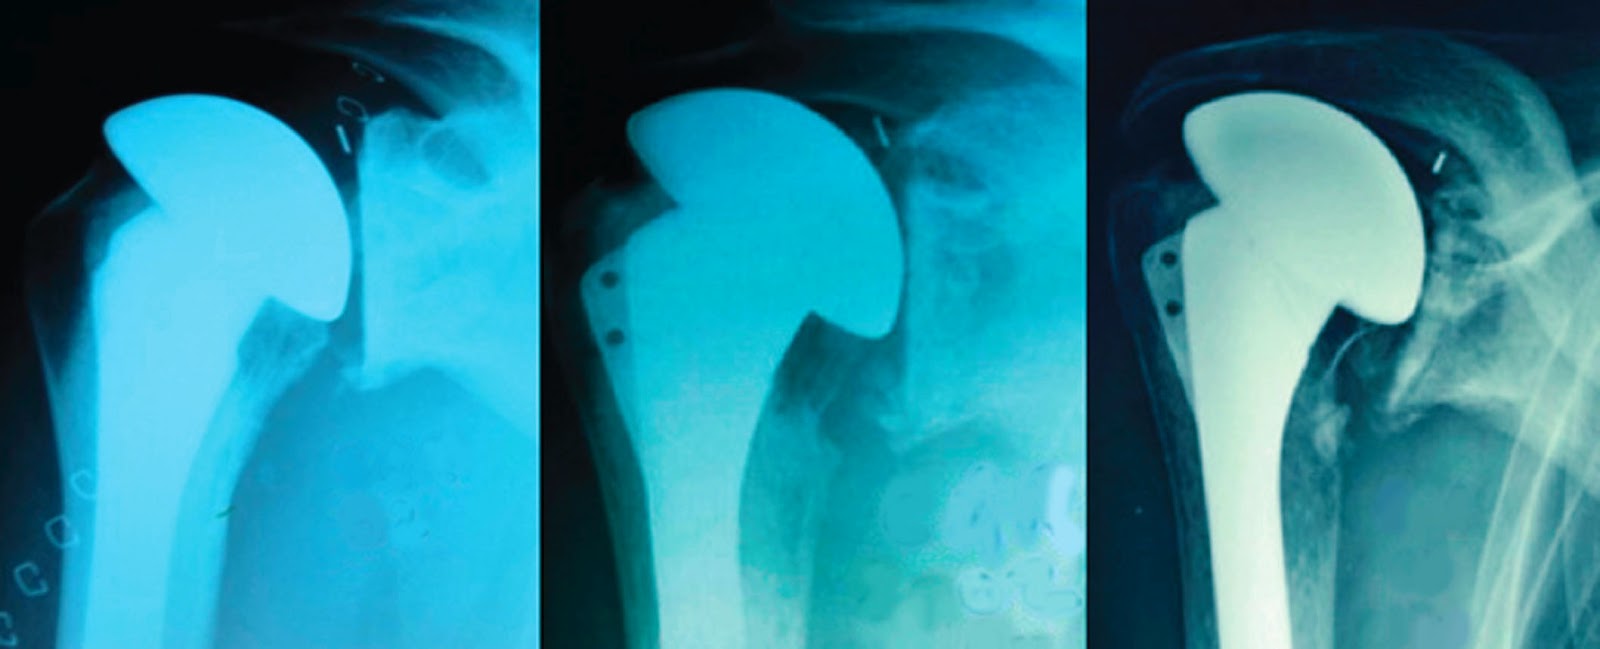

Is Shoulder Replacement More Painful Than Rotator Cuff Surgery . Shoulder replacement removes part or all. Both rotator cuff repair and shoulder replacement surgery are excellent operations for patients with shoulder pain. Which operation you need is dependent on what the cause of your. Pain is a likely side effect of both surgeries. Is shoulder replacement more painful than rotator cuff surgery? Total shoulder replacement, also known as total shoulder arthroplasty, is a procedure where portions of the bones in the shoulder joint are removed and replaced with. Studies have shown that both shoulder replacement and rotator cuff surgery provide lasting pain relief and. Rotator cuff surgery and shoulder replacement surgery are viable options for shoulder injuries and pain.

Total shoulder replacement, also known as total shoulder arthroplasty, is a procedure where portions of the bones in the shoulder joint are removed and replaced with. Is shoulder replacement more painful than rotator cuff surgery? Both rotator cuff repair and shoulder replacement surgery are excellent operations for patients with shoulder pain. Shoulder replacement removes part or all. Pain is a likely side effect of both surgeries. Rotator cuff surgery and shoulder replacement surgery are viable options for shoulder injuries and pain. Which operation you need is dependent on what the cause of your. Studies have shown that both shoulder replacement and rotator cuff surgery provide lasting pain relief and.